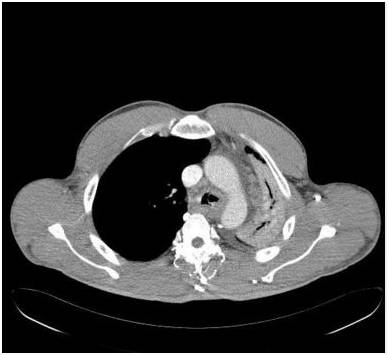

胸部前后位示弥漫不均匀的异常密度影,左肺体积缩小,左肺门区肿块样影与心膈角呈钝角。未增强纵隔窗CT示左肺肺不张,左主支气管完全受阻。增强CT示左主支气管及其段支气管内非强化的肿块。最小密度投影示左肺叶远端支气管重度狭窄,左主支气管及以下层面受阻。